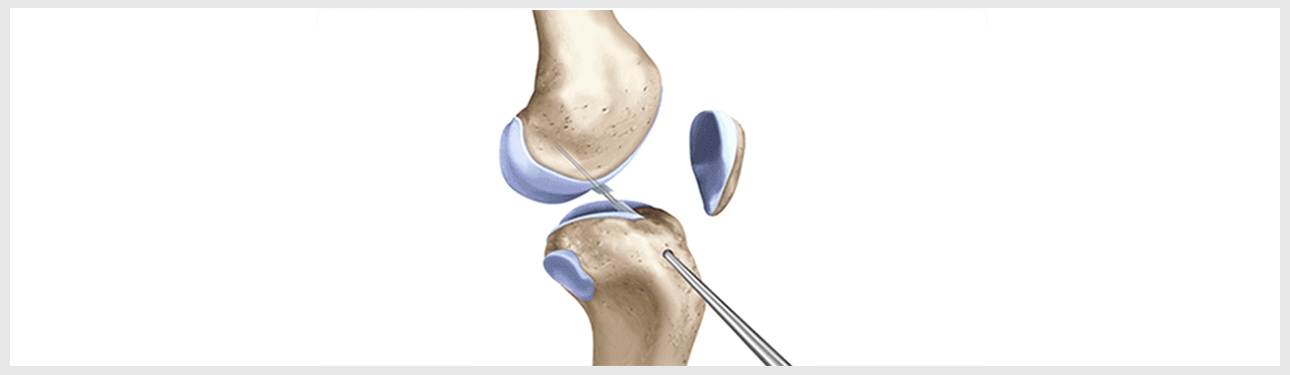

- 최소 절개로 대퇴골과 경골의 병변 부위에 구멍을 내줍니다.

- 터널 구멍을 이용해 이식건을 통과시켜 넣습니다.

- 삽입된 인대를 당긴 후 양측에서 고정하여 새로운 인대 조직이 원래의 인대 강도를 유지하도록 잡아줍니다.